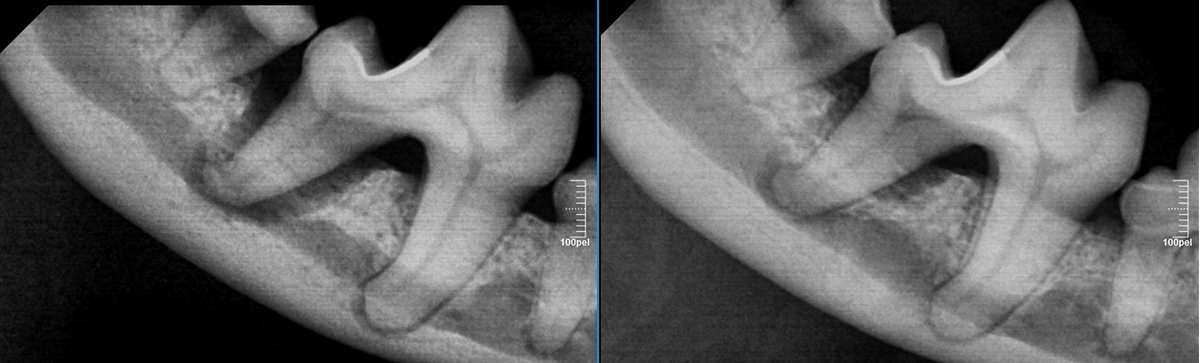

우리가 관찰하는 아이의 치아는 전체중 아주 일부분입니다.

치아의 뿌리, 치아를 둘러싼 뼈와 인대는 치아방사선으로만 확인이 가능하기 때문에 정확한 치과치료를 위해선 반드시 촬영이 필요 합니다.

치아방사선 사진